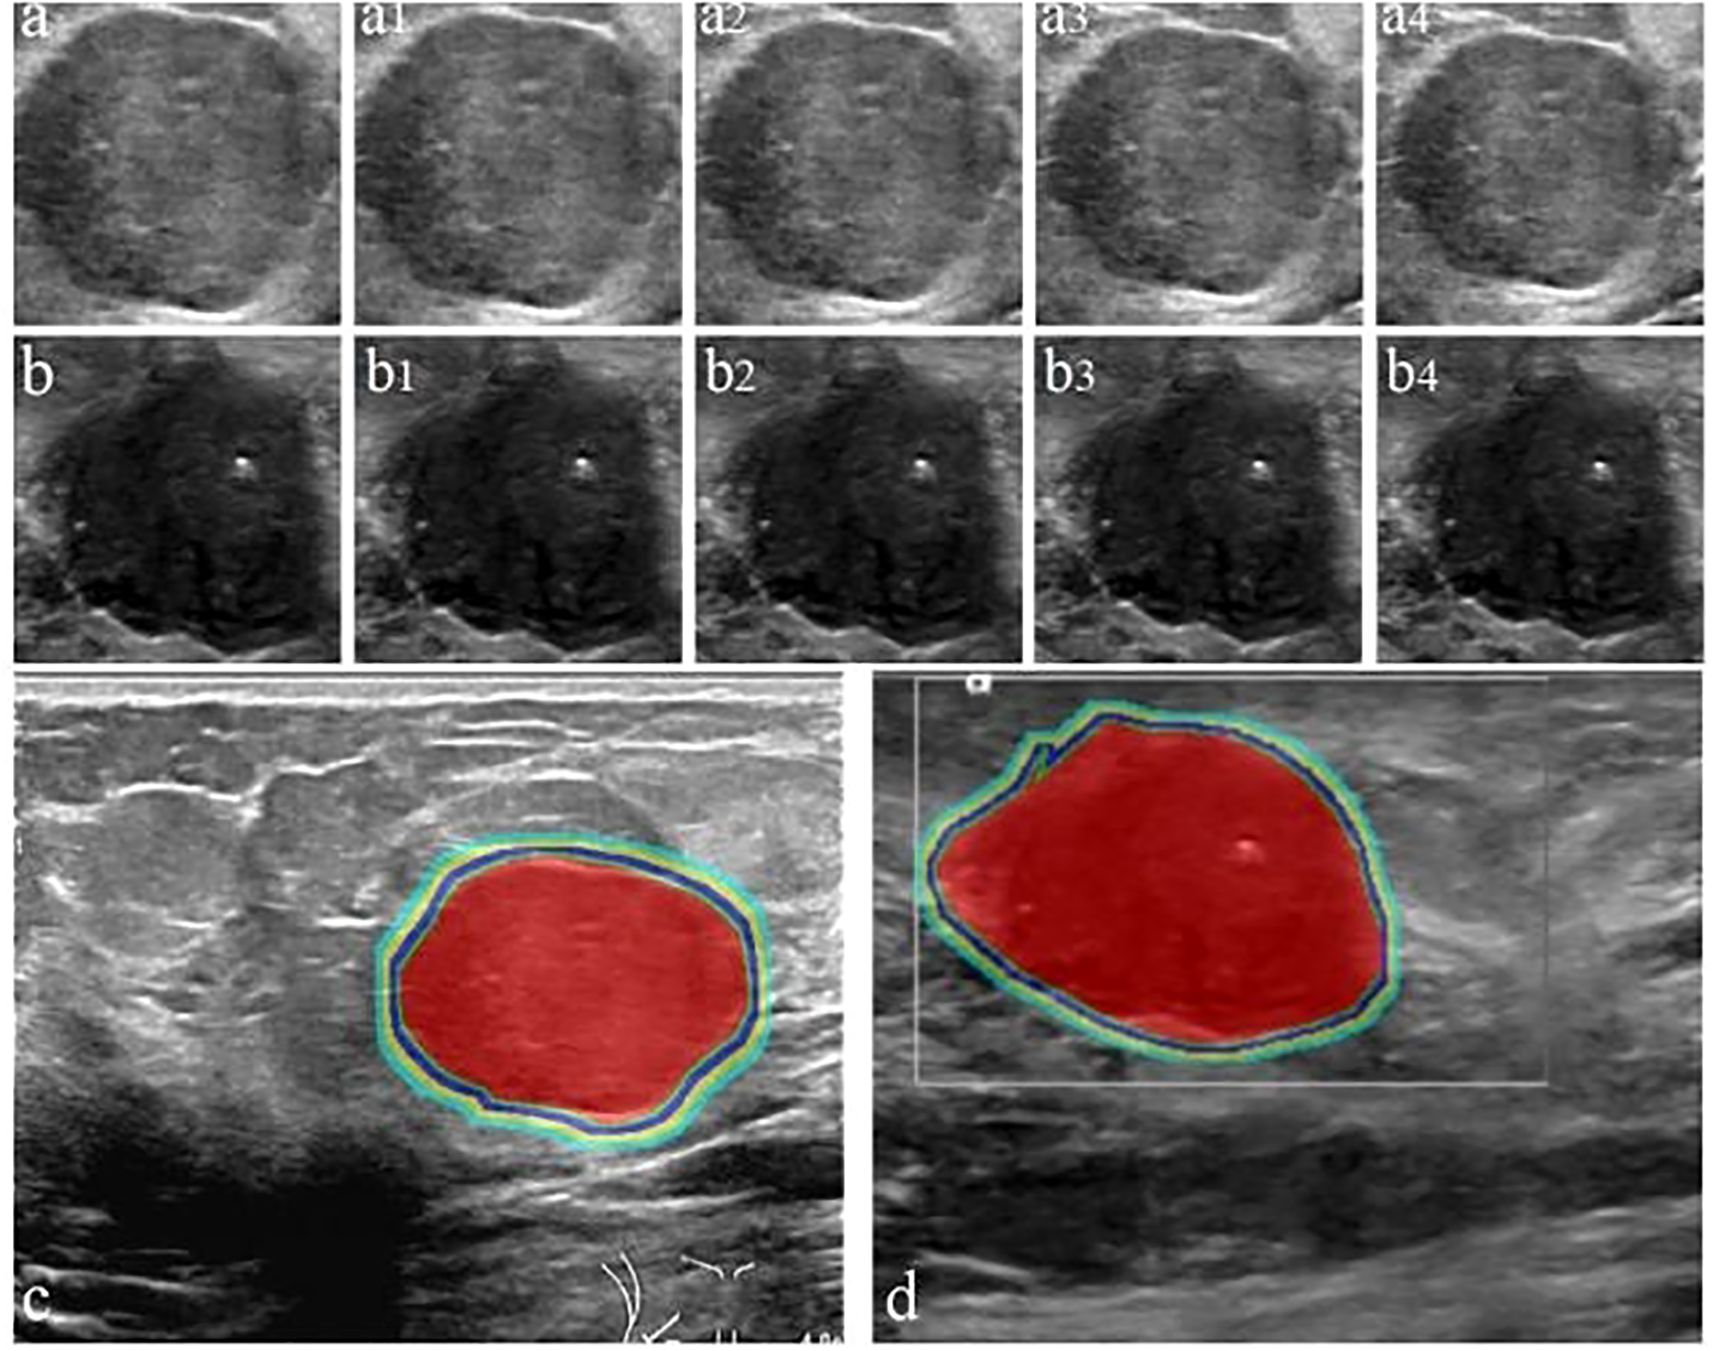

ROI delineation and image segmentation were performed manually using ITK-SNAP (v3.80) by three ultrasound specialists with >10 years of experience, guided by a senior physician (>20 years experience). Inter- and intra-observer variability was assessed using Dice Similarity Coefficient (DSC) and Intraclass Correlation Coefficient (ICC); results indicated good to excellent agreement (DSC: 0.78-0.93, ICC: 0.832-0.949), and no statistically significant bias was found in feature extraction between observers (p > 0.05 for most features). The ITR was delineated layer-by-layer, avoiding necrosis. PTR was generated by expanding the ITR outward by 4mm, 8mm, 12mm, and 16mm using the Onekey AI platform (22) and MATLAB 2016b (23). The rationale for selecting these PTR thicknesses was based on prior literature suggesting stromal involvement within these distances (24, 25) and exploratory analysis showing varying predictive power across these ranges (see Sensitivity Analysis in Section 2.6). PTR extending beyond breast parenchyma was manually removed. Disagreements were resolved by consensus. Examples are shown in Figures 2–4.

Figure 3. Workflow for delineating ITR and PTR in FA and PT patients under different ROI segmentation schemes: FA (a) and PT (b); red areas represent ITR, yellow-green areas represent 4 mm, 8 mm, 12 mm, and 16 mm PTR in FA (c) and PT (d). ITR: intratumoral area; PTR: peritumoral area.